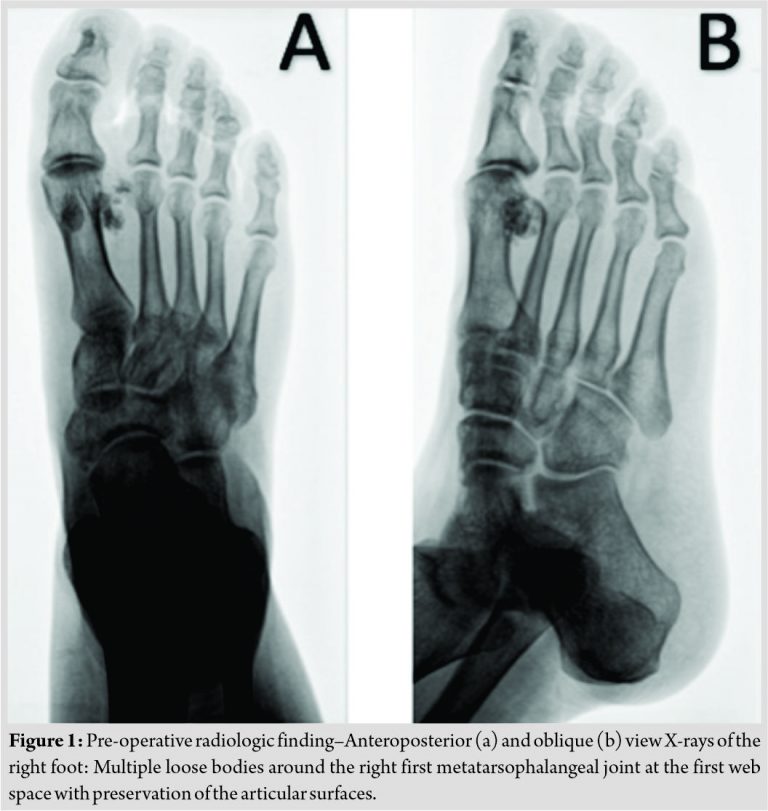

Examination confirmed a tender fixed mass on the dorsal aspect of the first webspace with slight swelling and no temperature or skin changes. The range of motion of the metatarsophalangeal joint was complete, although movement was painful in all positions. The rest of the examination was unremarkable. Plain radiographs of the foot showed multiple oval ossified lesions adjacent to the lateral side of the first metatarsal head in the first webspace, with bone remodeling of the first metatarsal head and a preserved joint line (Fig. 1). Computed tomography (CT)scan showed a multiple lobulated soft tissue mass with curvilinear calcification around the head of the first metatarsal (Fig. 2).